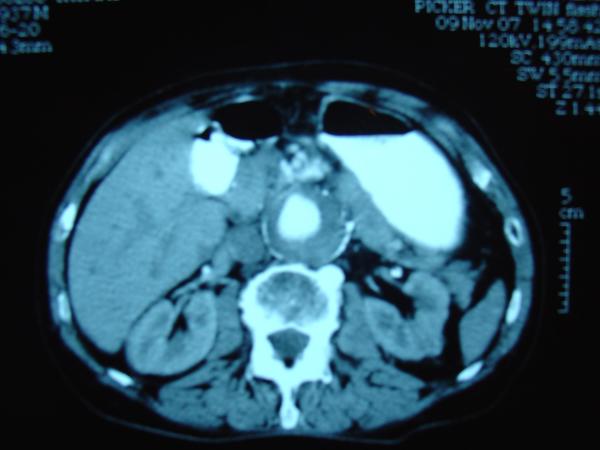

Endovascular repair of anastomotic abdominal aortic aneurysm, after aortobifemoral bypass

Vascular Clinic, Naval and Veterans Hospital of Athens

AVEM2009-Thessaloniki